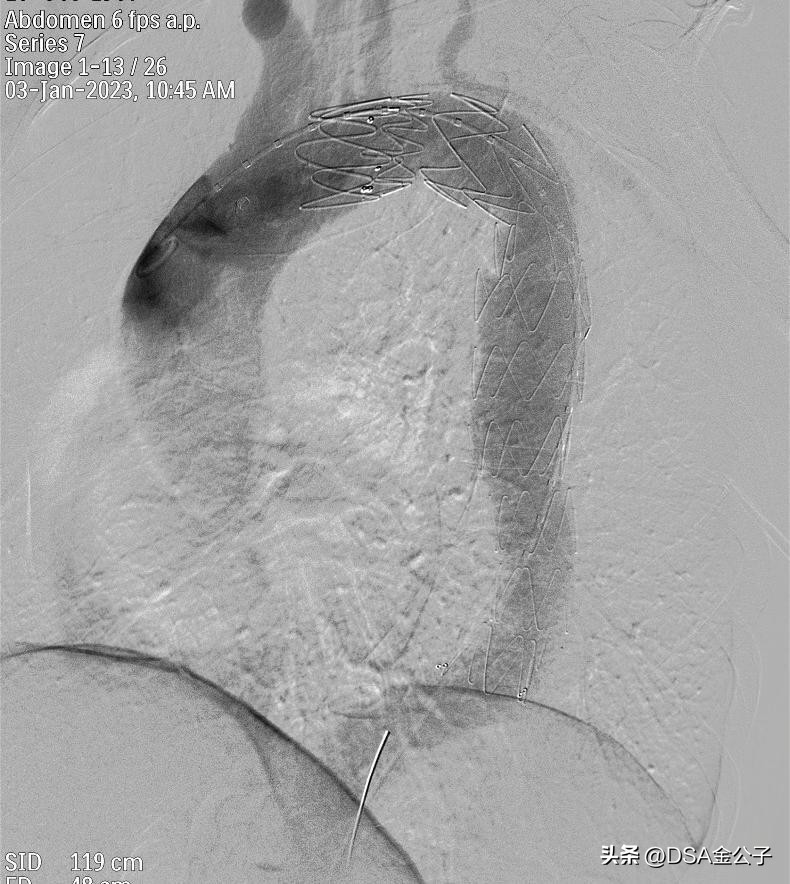

Ⅲ型主动脉夹层:介入胸主动脉支架置入或腹主动脉支架置入。

植入支架后,动脉瘤消失